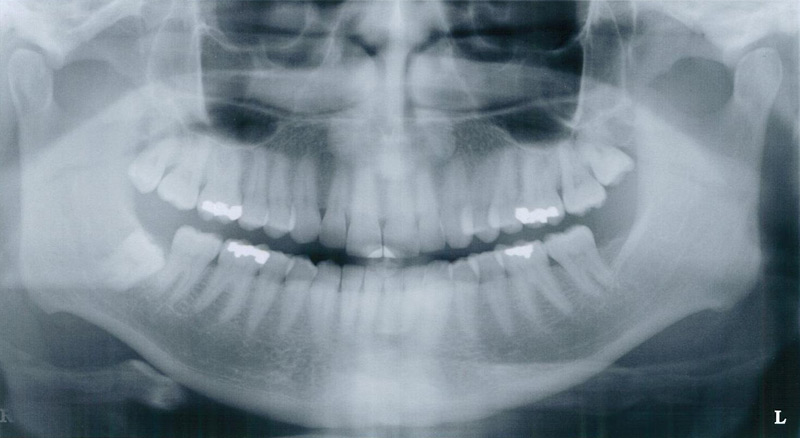

Bitewings

The bitewing x-ray is commonly used to detect decay, and may be used in the general dentist's screening in conjunction with the panograph. It shows the crowns of the upper and lower teeth at the same time, and shows good detail. Normally 4 films are taken. Unfortunately, the bone is often not visible, which limits the usefulness of bitewings in periodontics. Bitewings are generally recommended every 6-12 months to check for decay.